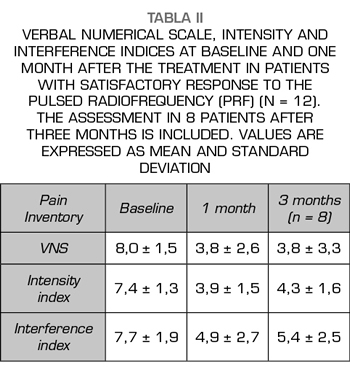

Results: The VNS score decreased from 7.7 ± 2,2 to 5.9 ± 3 (p < 0.01). Intensity and Interference Scores were reduced from 7.1 ± 1.5 to 5.9 ± 2.1 (p < 0.01) and 7.1 ± 1.9 to 6.0 ± 2.3 (p < 0.02) respectively. In 12 patients (40 %) a satisfactory analgesic response was observed. In these patients the VNS decreased from 8.0 ± 1.5 to 3.8 ± 2.6. Intensity and Interference Scores were reduced from 7.4 ± 1.3 to 3.9 ± 1.5 (p < 0.0001) y 7.7 ± 1.9 to 4.9 ± 2,7 (p = 0.002) respectively.

The score in the VNS prior to the procedure was reduced from 7.7 ± 2.2 to 5.9 ± 3 (p <0.01, t test for paired samples), taking into account the entire sample (n = 30), which implies a variation of 23% (Table I, Figure 3). The Intensity Index decreased from 7.1 ± 1.5 to 5.9 ± 2.1 (p <0.01), which implies a change of 16%, while the Interference Index decreased by 15% (7.1 ± 1.9 to 6.0 ± 2.3) (p <0.02) (Table I, Figures 4 and 5). When evaluating the patients who responded favorably using VNS, 12 out of 30 patients showed a decrease of at least 2 points on that scale, representing 40% of the sample. If we analyze these patients separately, we can observe that the initial values of VNS decreased from 8.0 ± 1.5 to 3.8 ± 2.6 after the procedure, which implies a reduction of 53% (Table II, Figure 6).

Ten out of these 12 patients showed a variation of three points or more in VNS (more than 50% variation), whereas only 2 patients had a variation of two points on the scale (30% variation). In this group of patients, the Intensity and Interference Indexes were reduced by 47% and 36%, respectively, from 7.4 ± 1.3 to 3.9 ± 1.5 (p <0.0001) for the Intensity Index and from 7.7 ± 1.9 to 4.9 ± 2.7 (p = 0.002) for the Interference Index (Table II, Figures 7 and 8). The 30 patients included reported an average of subjective improvement of 59%. No complications of the procedures were recorded in these cases.

In eight patients with a satisfactory outcome after one month, a three-month evaluation of the procedures was conducted. In these, the VNS remained at low values, 3.8 ± 3.3 (p = 0.007), something similar happened with the Intensity and Interference Indexes, being 4.3 ± 1.6 and 5.4 ± 2.5, respectively (p = 0.001 and p = 0.02, when compared with the baseline values (Figures 6, 7 and 8).